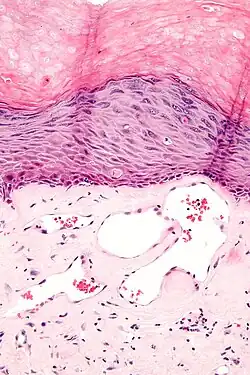

Angiokeratomas characteristically have large dilated blood vessels in the superficial dermis and hyperkeratosis (overlying the dilated vessels).

Scrotal angiokeratoma; visible large dilated blood vessels and hyperkeratosis

Scrotal angiokeratoma; visible large dilated blood vessels and hyperkeratosis -

Scrotal angiokeratoma (Fordyce type); dilated cavernous capillaries, acanthosis